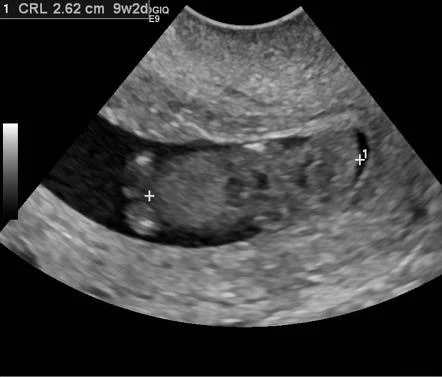

- Transabdominal/TVUSS:

- a single ultrasound scan can diagnose a miscarriage if there is a pregnancy within the uterine cavity.